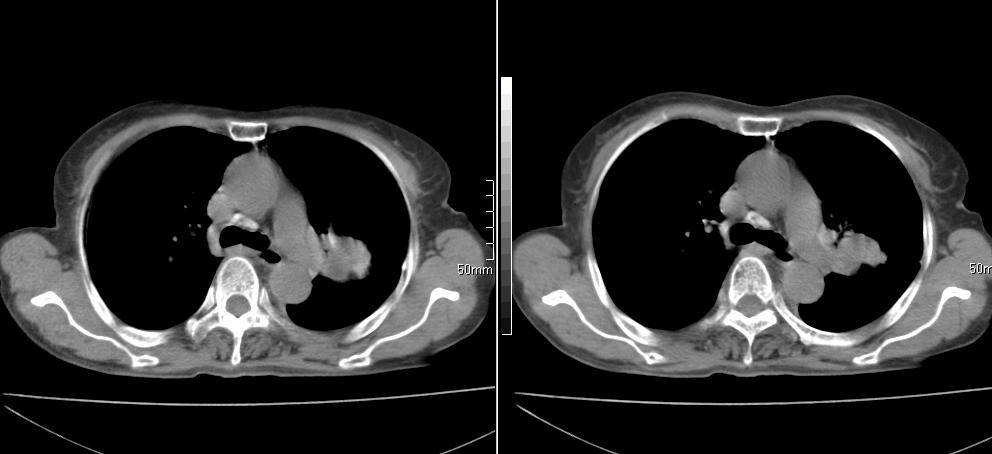

标题: CT26857:女,60岁,胃部不适前来就诊,不咳嗽,乏力,胸椎 [打印本页]

标题: CT26857:女,60岁,胃部不适前来就诊,不咳嗽,乏力,胸椎

1、胸椎有骨质破坏伴周软组织,考虑胸椎转移。2、考虑左肺上叶尖后段支气管开口区周围型肺癌可能。

1、胸椎有骨质破坏伴周软组织,考虑胸椎转移。2、考虑左肺上叶尖后段支气管开口区周围型肺癌可能。建议行纤支镜检查!

1、胸椎有骨质破坏伴周软组织,考虑胸椎转移。2、考虑左肺中央型肺癌可能。

支持中央型肺癌,胸椎转移。

1)考虑左肺中央型肺癌。2)胸椎转移瘤不排除;建议行mri检查。